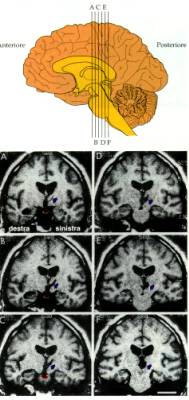

Ippocampo e memoria

umana.

Lesioni dellippocampo in H.M., un

celebre caso di amnesia studiato da B. Milner

W.B. Scoville e B. Milner, Loss of recent

memory after bilateral hippocampal lesions. Journal of Neurology,

Neurosurgery and Psychiatry, 20, 11-21, 1965

Brenda Milner e il MQ (Memory

Quotient):

si parla di amnesia quando una persona

dimostra un MQ più basso di 15 punti dellIQ: nel caso di

HM, che aveva un quoziente di intelligenza medio, la differenza tra

lIQ e il MQ era di ben 47 punti.